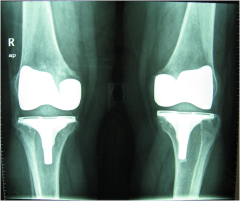

Αμφοτερόπλευρη ολική αρθροπλαστική γόνατος

Σε προχωρημένα στάδια ή λύση είναι χειρουργική. Σε ορισμένες περιτπώσεις και σε σχετικά νέους ασθενείς με οστεοαρθρίτιδα γόνατος μπορεί να γίνει οστεοτομία της κνήμης. Στις υπόλοιπες περιπτώσεις οστεοαρθρίτιδας γόνατος αλλά και ισχίου προτιμότερη θεραπεία είναι η ολική αρθροπλαστική. Υπάρχουν διάφοροι τύποι ολικών αρθροπλαστικών. Το χαρακτηριστικό τους είναι ότι ανακουφίζουν τον/την ασθενή από τον πόνο και έως κάποιο βαθμό βελτιώνουν και την κινητικότητά του.

Ειδικά για την αρθροπλαστική γόνατος χρησιμοποιώ ρομποτικά υποβοηθούμενη μέθοδο (navigation) που παρέχει μεγαλύτερη ακρίβεια στις διεγχειρητικές οστεοτομίες και συνεπώς καλύτερο αποτέλεσμα.

Οι αρθροπλαστικές γίνονται με διάφορες μεθόδους αναισθησίας και η παραμονή στο νοσοκομείο είναι ολιγοήμερη. Η βάδιση με τη χρήση κάποιου υποβοηθητικού μέσου επιτρέπεται από τις πρώτες μέρες.